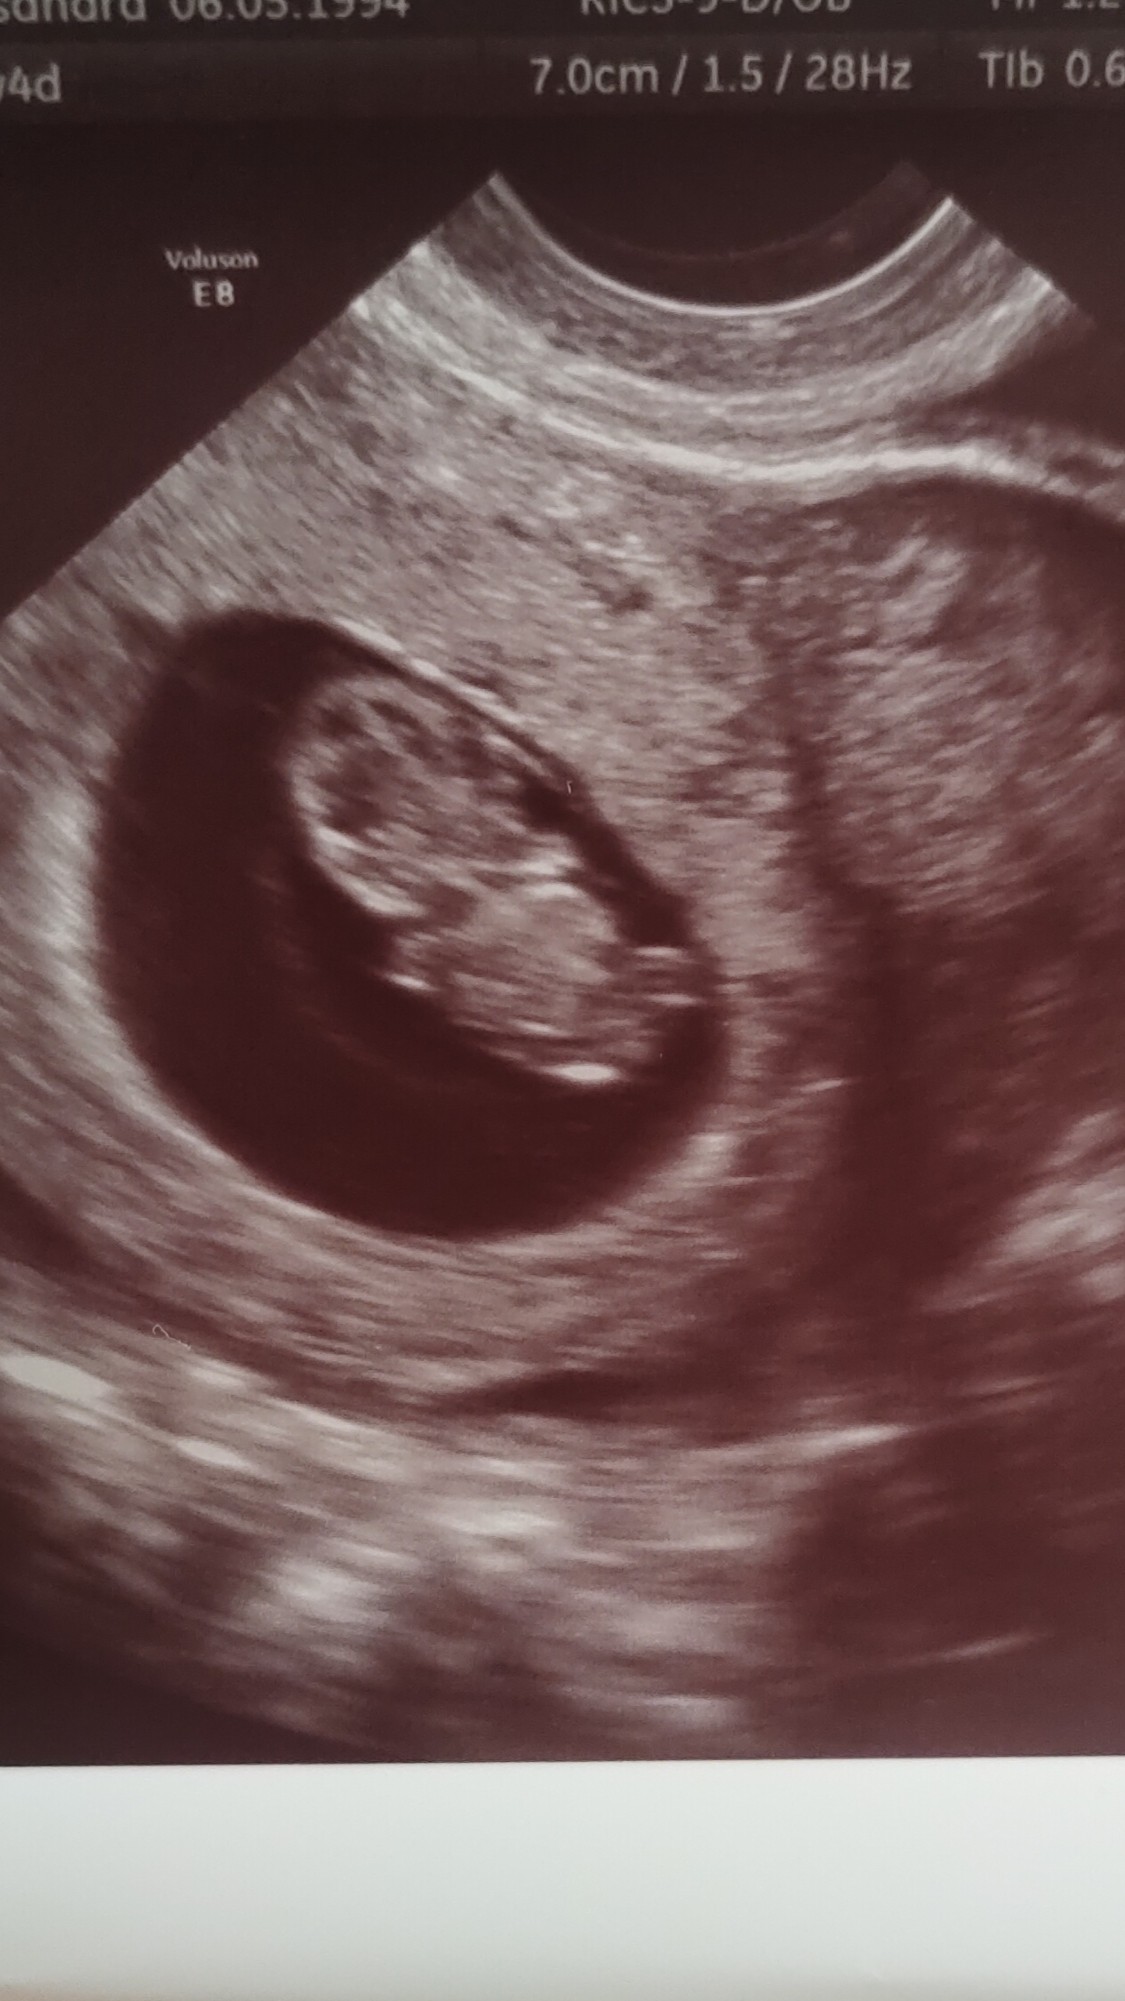

Hej Dziewczyny, melduję się po pierwszym USG prenatalnym i tym samym pierwszym moim przez powłoki brzuszne 🙂 na samym usg wszystko git, maluszek sobie radośnie podskakiwał 😁 taki z niego śmieszek. Ma rączki i nóżki i lekarz nie stwierdził żadnych nieprawidłowości. Oficjalne wyniki, że tak powiem, bo to dopiero w zestawieniu z wynikami krwi, za 1,5 tygodnia.

Jeden maleńki minus jest taki, że krew pobierała jakoś bardzo mało doświadczona kobietka, widać było zresztą, że bardzo młoda i tak mi nieszczęśliwie tą krew pobrała, że mam siniaka i mnie ręka trochę boli. Kurna to jak miałam zestaw badań z krwi, gdzie dużo mi jej pobierali, to nic nie czułam, a tu taka lipa. No ale może każdy musi się nauczyć